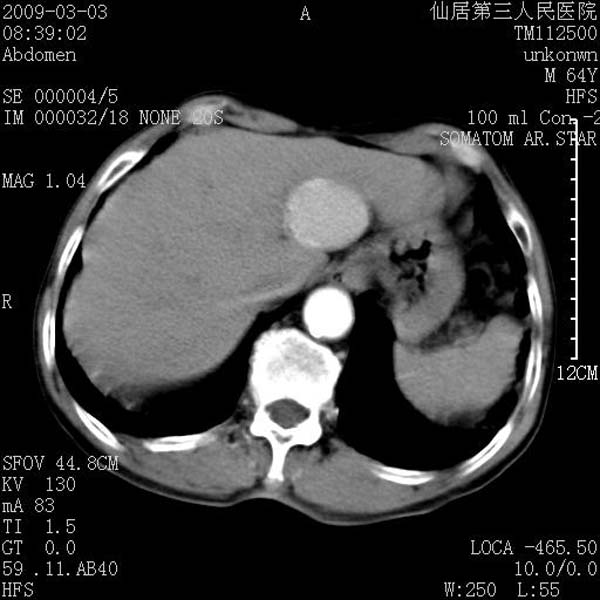

标题: CT18469:男性,64y,体检B超示肝脏低回声肿块,有胃溃疡手术 [打印本页]

患者,男性,64y,体检b超示肝脏低回声肿块,有胃溃疡手术史。

考虑----胃肠道间质瘤可能性大

从平扫及增强的特点来看,支持肝脏腺瘤并出血。

考虑胃间质瘤可能性大。

胃肠道间质瘤!

ct值呢?感觉没强化,象囊性。

考虑肝静脉韧带裂区良性占位性病变(囊肿?)。

考虑肝囊肿并出血可能性大.

考虑高密度囊肿可能性大